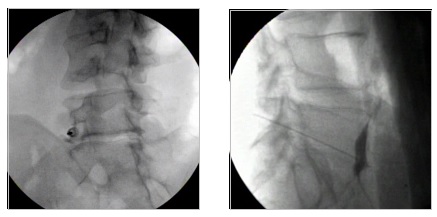

Με τον ασθενή σε πρηνή θέση και υπό ακτινοσκοπικό έλεγχο, στην πρώτη προσπέλαση η βελόνα προωθείται εκατέρωθεν από το κατώτερο πλάγιο τμήμα του Ο5 σπονδύλου και το άκρο της φθάνει ακριβώς μπροστά από τον Ο5 σπόνδυλο, ενώ στη δεύτερη προσπέλαση, η βελόνα φθάνει μπροστά από τον σπόνδυλο , περνώντας μέσα από το μεσοσπονδύλιο δίσκο του Ο5-Ι1 διαστήματος.

Αμέσως μετά άφιξη της βελόνας στο σημείο-στόχο, δίνεται σκιαγραφική ουσία και ακολουθεί η χορήγηση του αναισθητικού διαλύματος. Επί επιτυχούς αποκλεισμού, ο ασθενής υποβάλλεται σε δεύτερο χρόνο σε θεραπεία με ραδιοσυχνότητες, το αποτέλεσμα της οποίας διαρκεί πάνω από ένα έτος συνήθως. Η καταστροφή του γαγγλίου μπορεί να γίνει και με έγχυση νευρολυτικών παραγόντων, όπως η αλκοόλη και η φαινόλη.